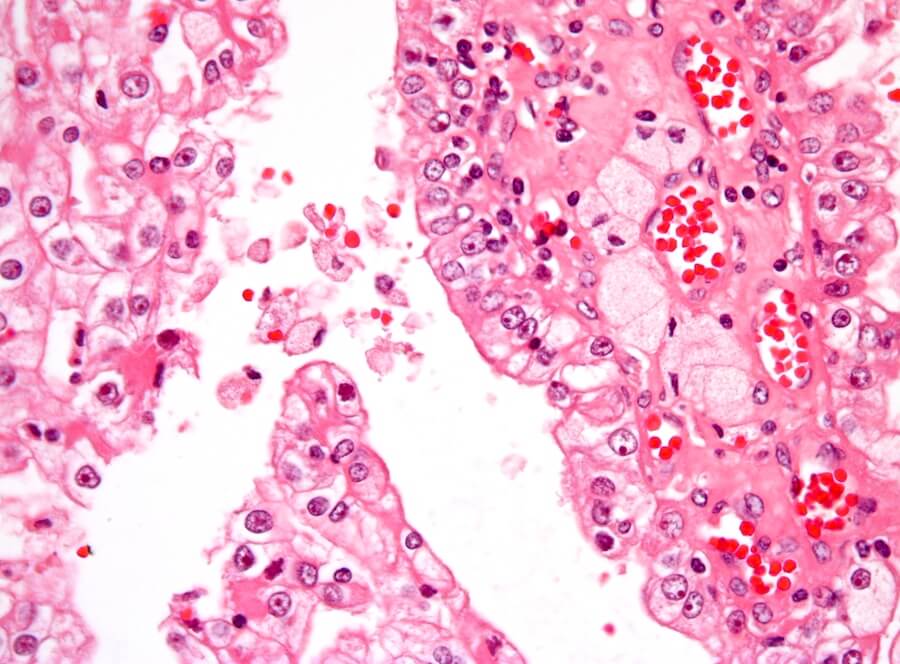

O câncer ocorre quando há uma multiplicação de células malignas fora de controle no corpo. O tipo mais comum de câncer renal na infância é chamado de tumor de Wilms ou nefroblastoma. É de consistência sólida e se origina no tecido renal imaturo.

Se indicado pelo especialista, realiza-se uma biópsia do tumor, puncionada com uma agulha para remover células ou tecido para análise microscópica por um patologista.